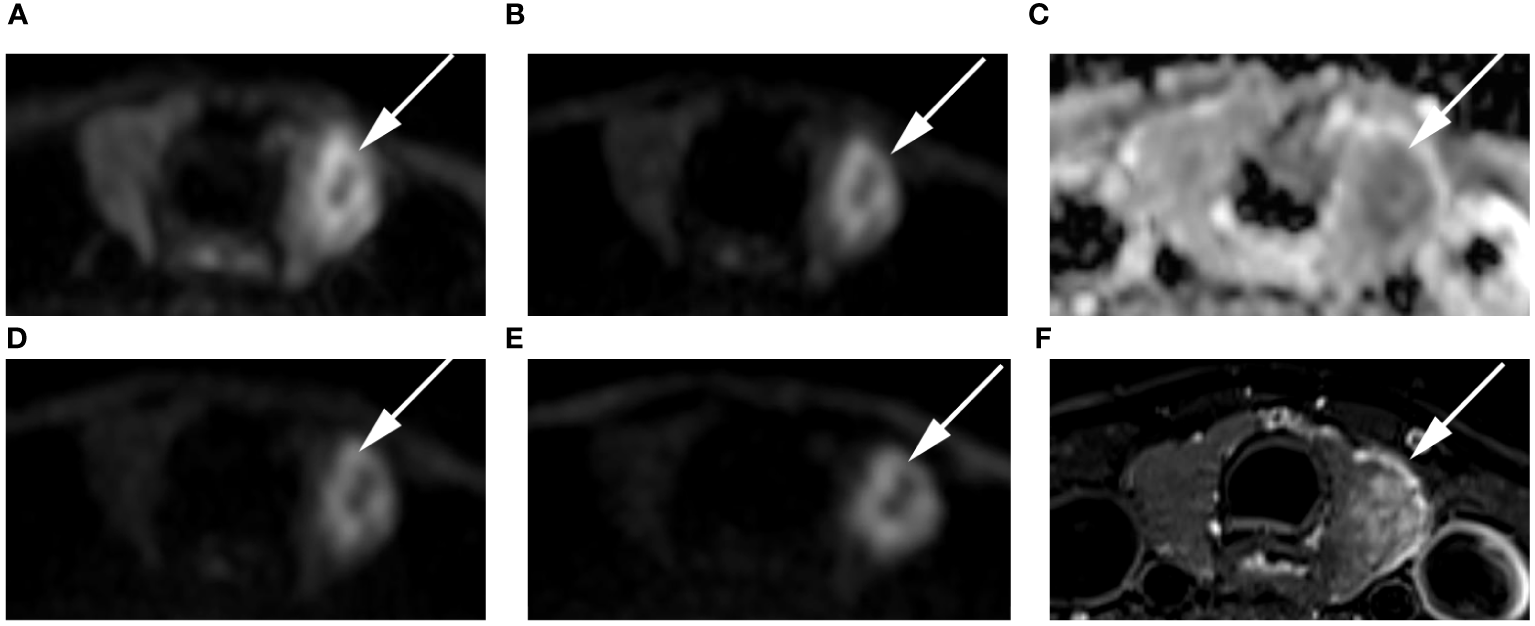

Figure 7 Images of a 24-year-old female with right lobe micropapillary carcinoma (arrow): DWI image with a b-value of 500 s/mm2 (A), 1000 s/mm2 (B), 1500 s/mm2 (D), 2000 s/mm2 (E); (C) ADC image with a b-value of 1500 s/mm2; (F) T2-weighted image. The SNR of the thyroid decreased as the b value increased. In the DWI image with a b-value of 1500 s/mm2, the SI of the nodule was significantly high relative to the other images.